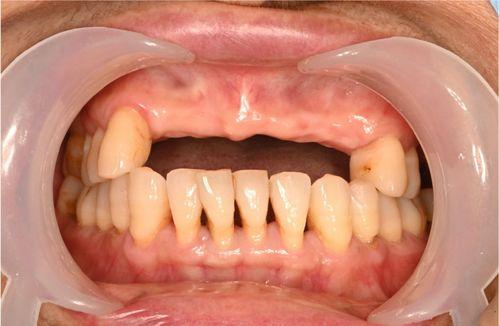

前牙缺失不僅影響咀嚼功能,還會對美觀造成較大影響,給患者的生活帶來諸多不便。因此,選擇合適的修復方法和牙冠材料至關重要。接下來,我們將詳細探討這兩個關鍵問題。

一、前牙缺失的修復方法

1.種植牙

(1)原理:通過在牙槽骨內植入人工種植體,待其與骨組織結合穩(wěn)固后,在種植體上安裝基臺和牙冠,從而恢復缺失牙齒的功能和美觀。

(2)優(yōu)點:穩(wěn)定性高,咀嚼效率接近天然牙,不損傷鄰牙,使用壽命長。

前牙缺失的修復方法